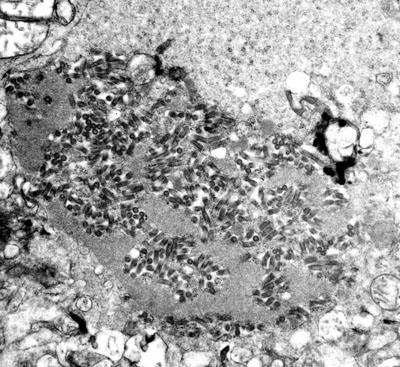

rabies A human bitten by an animal with rabies will almost certainly die within days unless immediately treated with a multi-stage vaccine regimen initially developed by Louis Pasteur in 1885. To combat the spread of rabies today, which nationwide affects over 40,000 people annually and countless wild and domestic animals, the United States spends over $300 million each year on its prevention and control. One important ecological feature that makes this disease difficult to contain is that animals with rabies tend to increase their ranges substantially after they become infected, and thus are more likely to come into contact with and bite other uninfected (or susceptible) animals. A challenging problem in the national battle against rabies is to determine the effect that this increase in mobility among infected animals has on the ability of the disease to persist over the course of an epidemic outbreak.

Small type: The study of these interacting susceptible and infected host sub-populations fit squarely within this year’s Evolution and Ecology theme at the MBI. The images seen here are in the public domain and some were obtained from the Public Health Image Library (PHIL) of the Centers for Disease Control and Prevention (CDC).